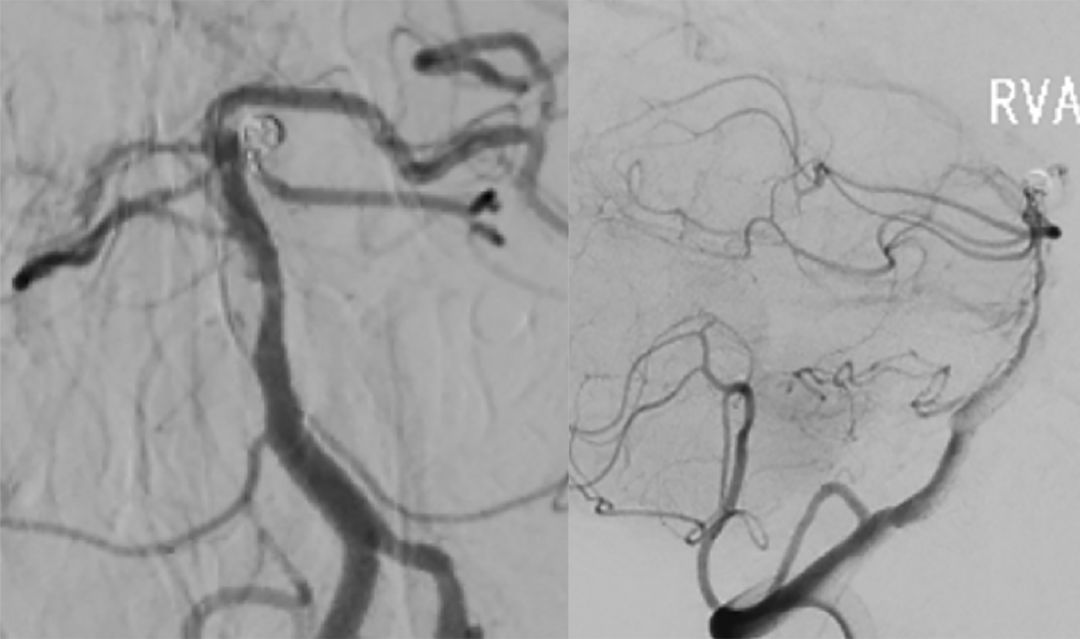

7. 术后造影显示动脉瘤完全栓塞,载瘤动脉通畅(图13)。

图13

2. 左侧小脑上动脉瘤体积较小,载瘤动脉较细,瘤颈稍窄,该动脉瘤处于基底动脉开窗的末端,不适合支架辅助栓塞动脉瘤,故单纯弹簧圈栓塞动脉瘤。